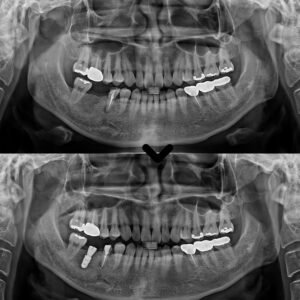

성남치과 남편 소개로 왔어요. 골다공증 환자분 뼈이식을 포함한 어금니 무절개 임플란트 사례

성남치과 남편 소개로 왔어요. 골다공증 환자분 뼈이식을 포함한 어금니 무절개 임플란트 사례 안녕하세요. 성남치과 서울박사치과입니다. 골다공증은 뼈의 밀도가 감소하고 뼈가 약해지는 질환으로, 주로 노년층에서 발생합니다. 이로 인해…